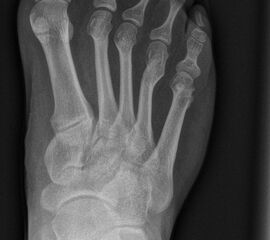

In der Regel bestehen aktive Wachstumsfugen bei Mädchen bis zum 12. und bei Jungen bis zum 14. Lebensjahr, mit Abweichungen von einem Jahr nach unten und nach oben. Präzise Informationen unter anderem darüber gibt das präoperative Röntgenbild (Abb. 2).

Abb. 2 a-c: offene Wachstumsfugen MT I Basis und Zehen (a), teilweise geöffnete Wachstumsfugen (b) und geschlossene Wachstumsfugen (c).

Zum Lesen der Bildbeschreibung und zur Vollansicht bitte die Bilder anklicken. Bilder: A. Helmers.